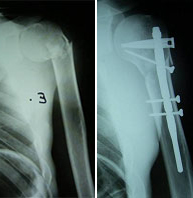

The shoulder region includes the clavicle, scapula and the proximal end of humerus. Fractures of the upper humerus are usually seen in patients of advanced age. In young patients shoulder fractures are associated with high-energy trauma and high risk sports where you have a direct impact of great violence such as climbing, motorcycling, cycling, skiing, rugby, soccer, etc.

Treatment depends on the fracture type and degree of displacement. Displaced fractures are usually subsidiaries of surgical treatment. In this case a surgery aimed at early mobilization with minimal risk of complications requires a great knowledge of joint biomechanics, meticulous handling of tissues adjacent to bone and the latest generation of osteosynthesis materials.